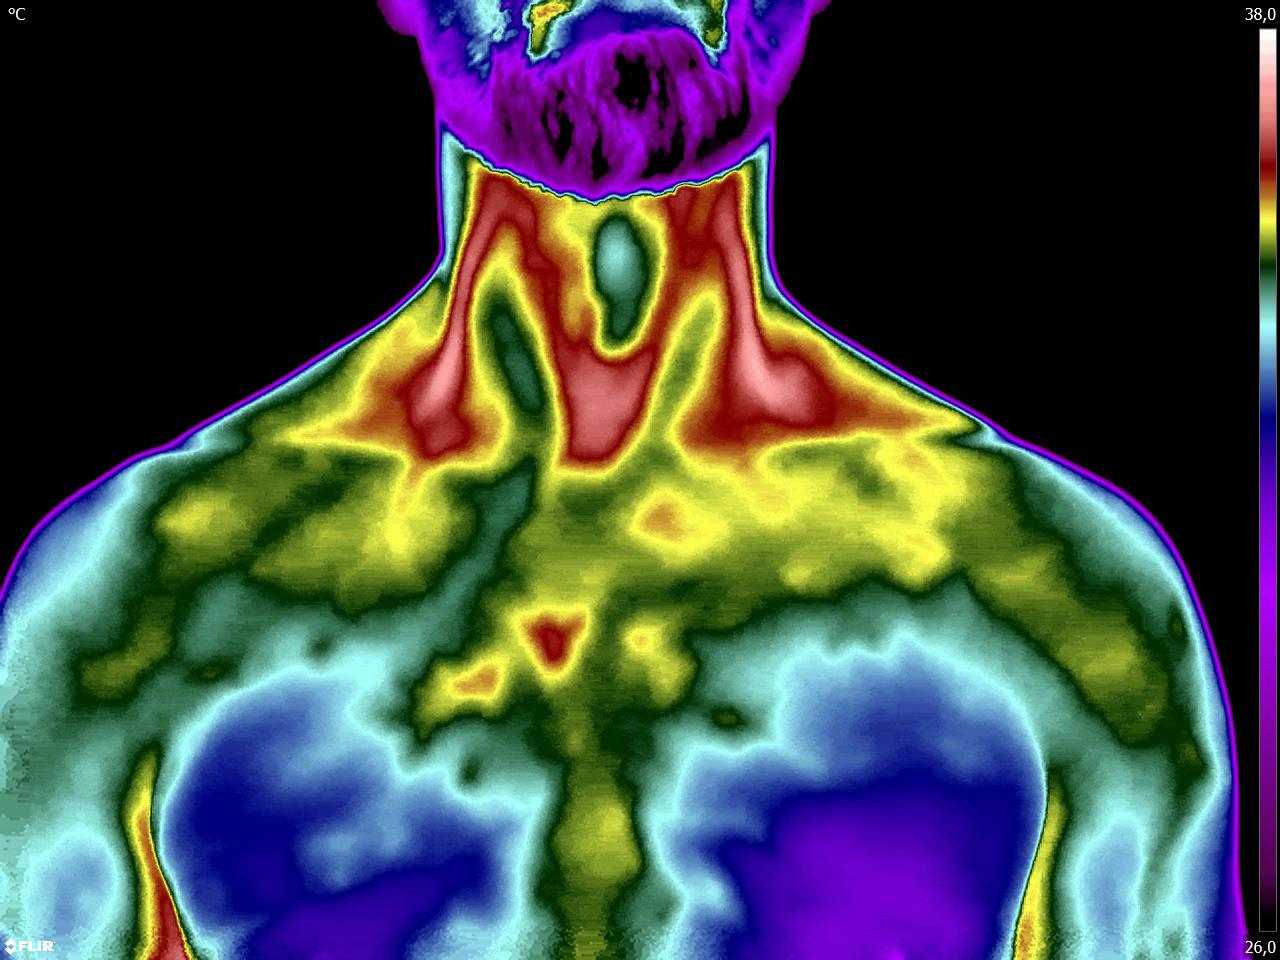

Como no caso dos termogramas abaixo de um paciente do sexo masculino, 44 anos, sem comorbidades e que apresentou dor em cervical. Foi realizado uma Análise Termofuncional e detectado alterações térmicas condizentes com o relato de dor.

Com estes achados foi possível determinar a cadeia postural que acometia o paciente, determinando o seu tratamento.

Somente com o conhecimento integral do Método de Termografia Infravermelha é possível detectar alterações e associá-las a uma disfunção.